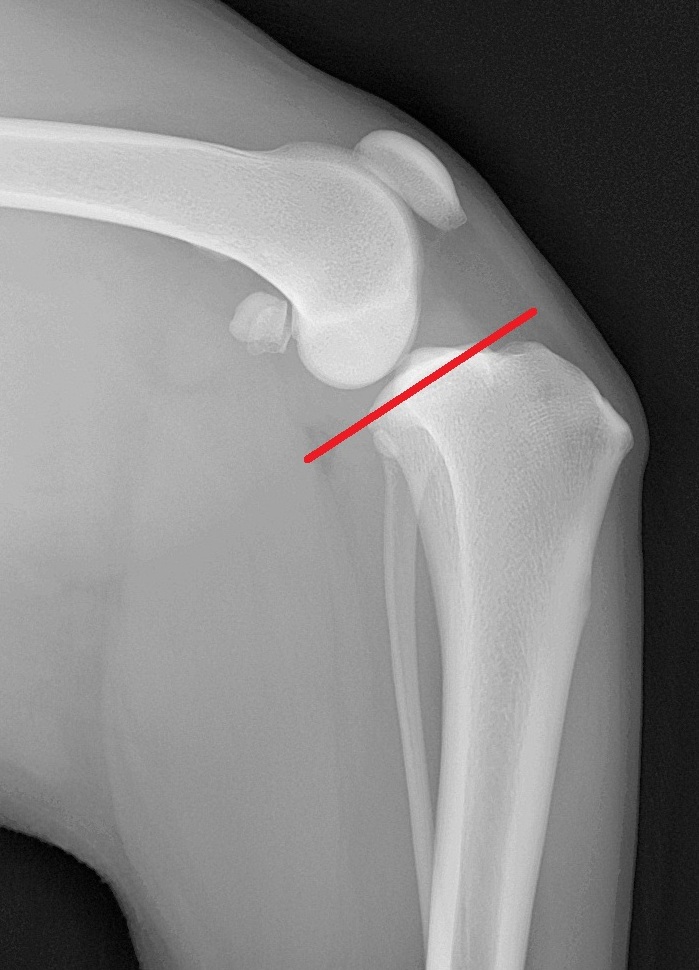

赤いラインが脛骨高平部角(TPA)で、通常は25°前後のワンちゃんが多いようです。この角度が大きくなると、前十字靭帯断裂のリスクが高くなるとも言われています。前十字靭帯断裂でTPAが大きい場合は、TPLO(脛骨高平部水平化骨切り術)という手術方法が術後経過が良いと報告されています。

カイちゃんはTPAが34°でしたので、TPLOを行いました。脛骨近位部を骨切りし、TPAを6°の角度にして特殊なプレートで固定します。TPAを6°前後に変更することで、脛骨の前方変位が起こらなくなり、膝の安定性が得られ早期に足を使うことが出来るようになります。

TPA34°